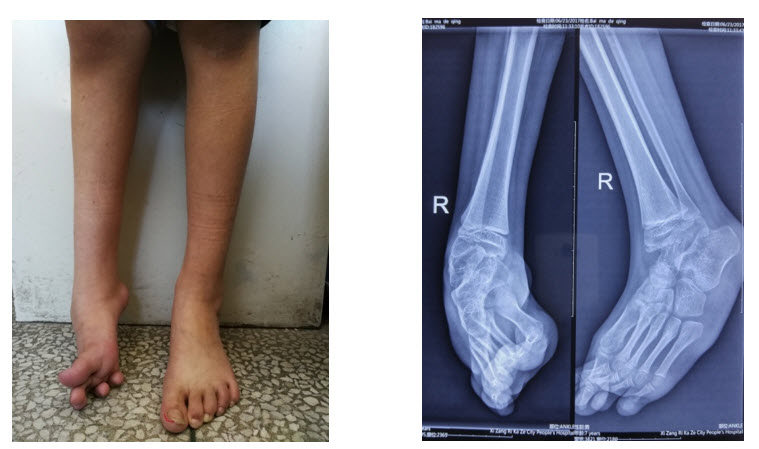

圖1:患兒站立位照 圖2:術(shù)前患足X片(右足高弓馬蹄內翻畸形)